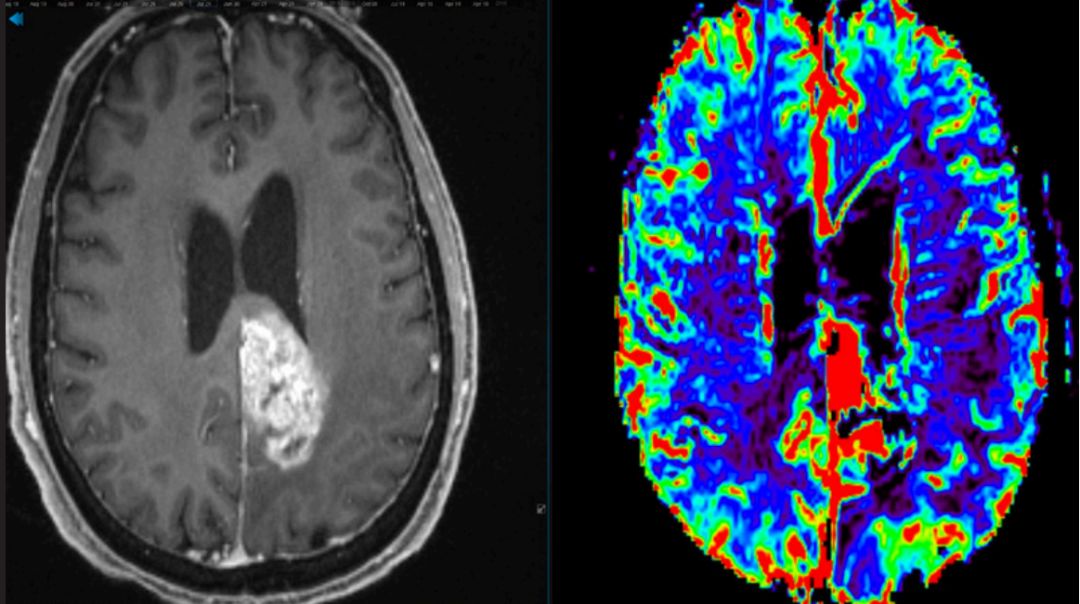

胶质母细胞瘤MRI影像图片。图源:American Brain Tumor Association,abta.org

胶质母细胞瘤(Glioblastoma,GBM),是一种原发性脑部肿瘤,死亡率极高,治愈率偏低,治疗预后差,易复发,是最难治疗的肿瘤之一(图1)